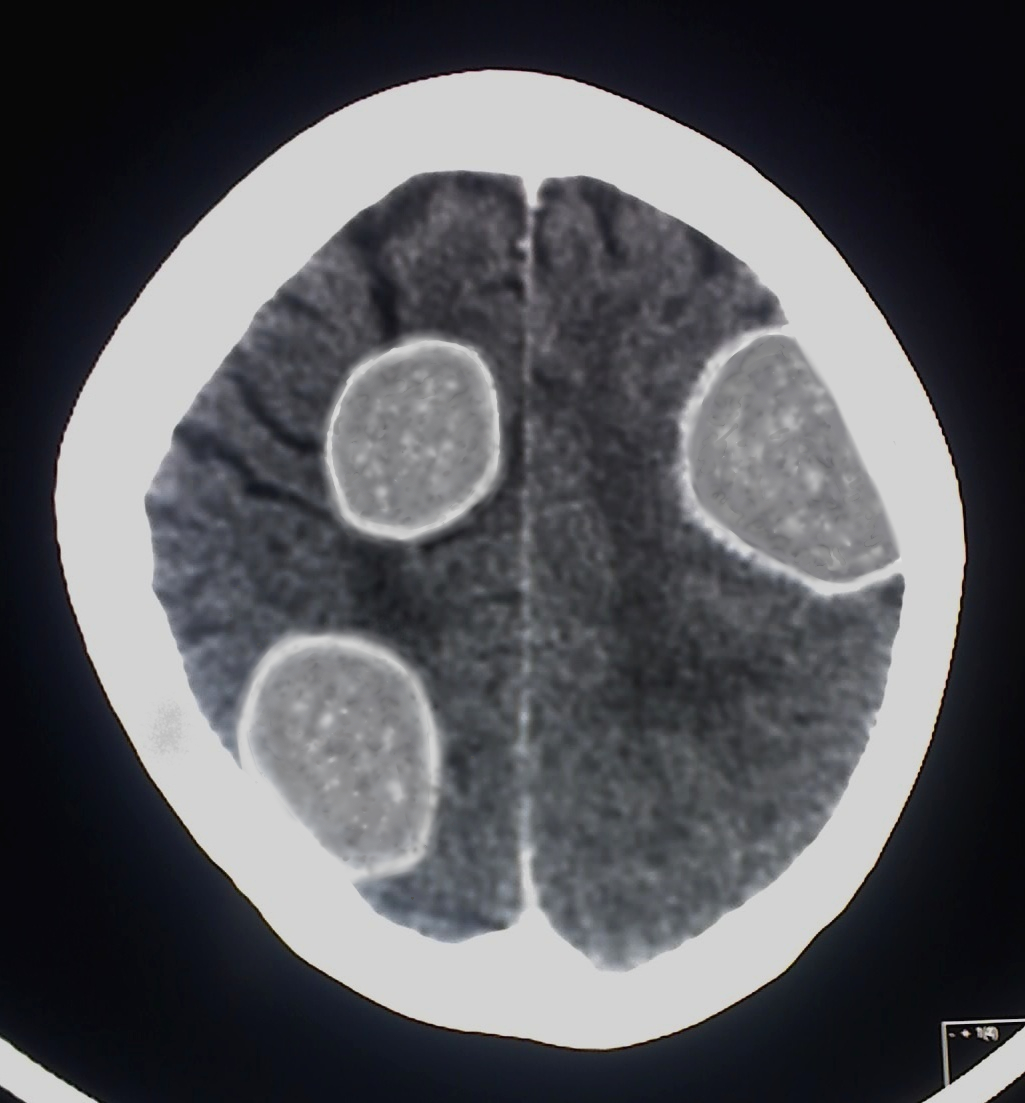

被寄生的宿主头部,卵壳形成时期的CT扫描图。

| 大约21~45天 | 肉体开始形成。覆盖胚盘的薄膜逐渐变为长球状,最终形成大约20mm×15mm的卵壳,包裹着胚盘。随着卵壳的形成,胚盘不断进行细胞分裂,在卵壳内部诞生出SCP-3283-JP的幼体。这种成长导致宿主的颅骨呈半球状凹陷,可能影响脑功能。然而,由于在头部皮肤内侧形成的营养供应器官起到了盖子的作用,除非触摸,否则在SCP-3283-JP孵化之前很难发现异常。 |